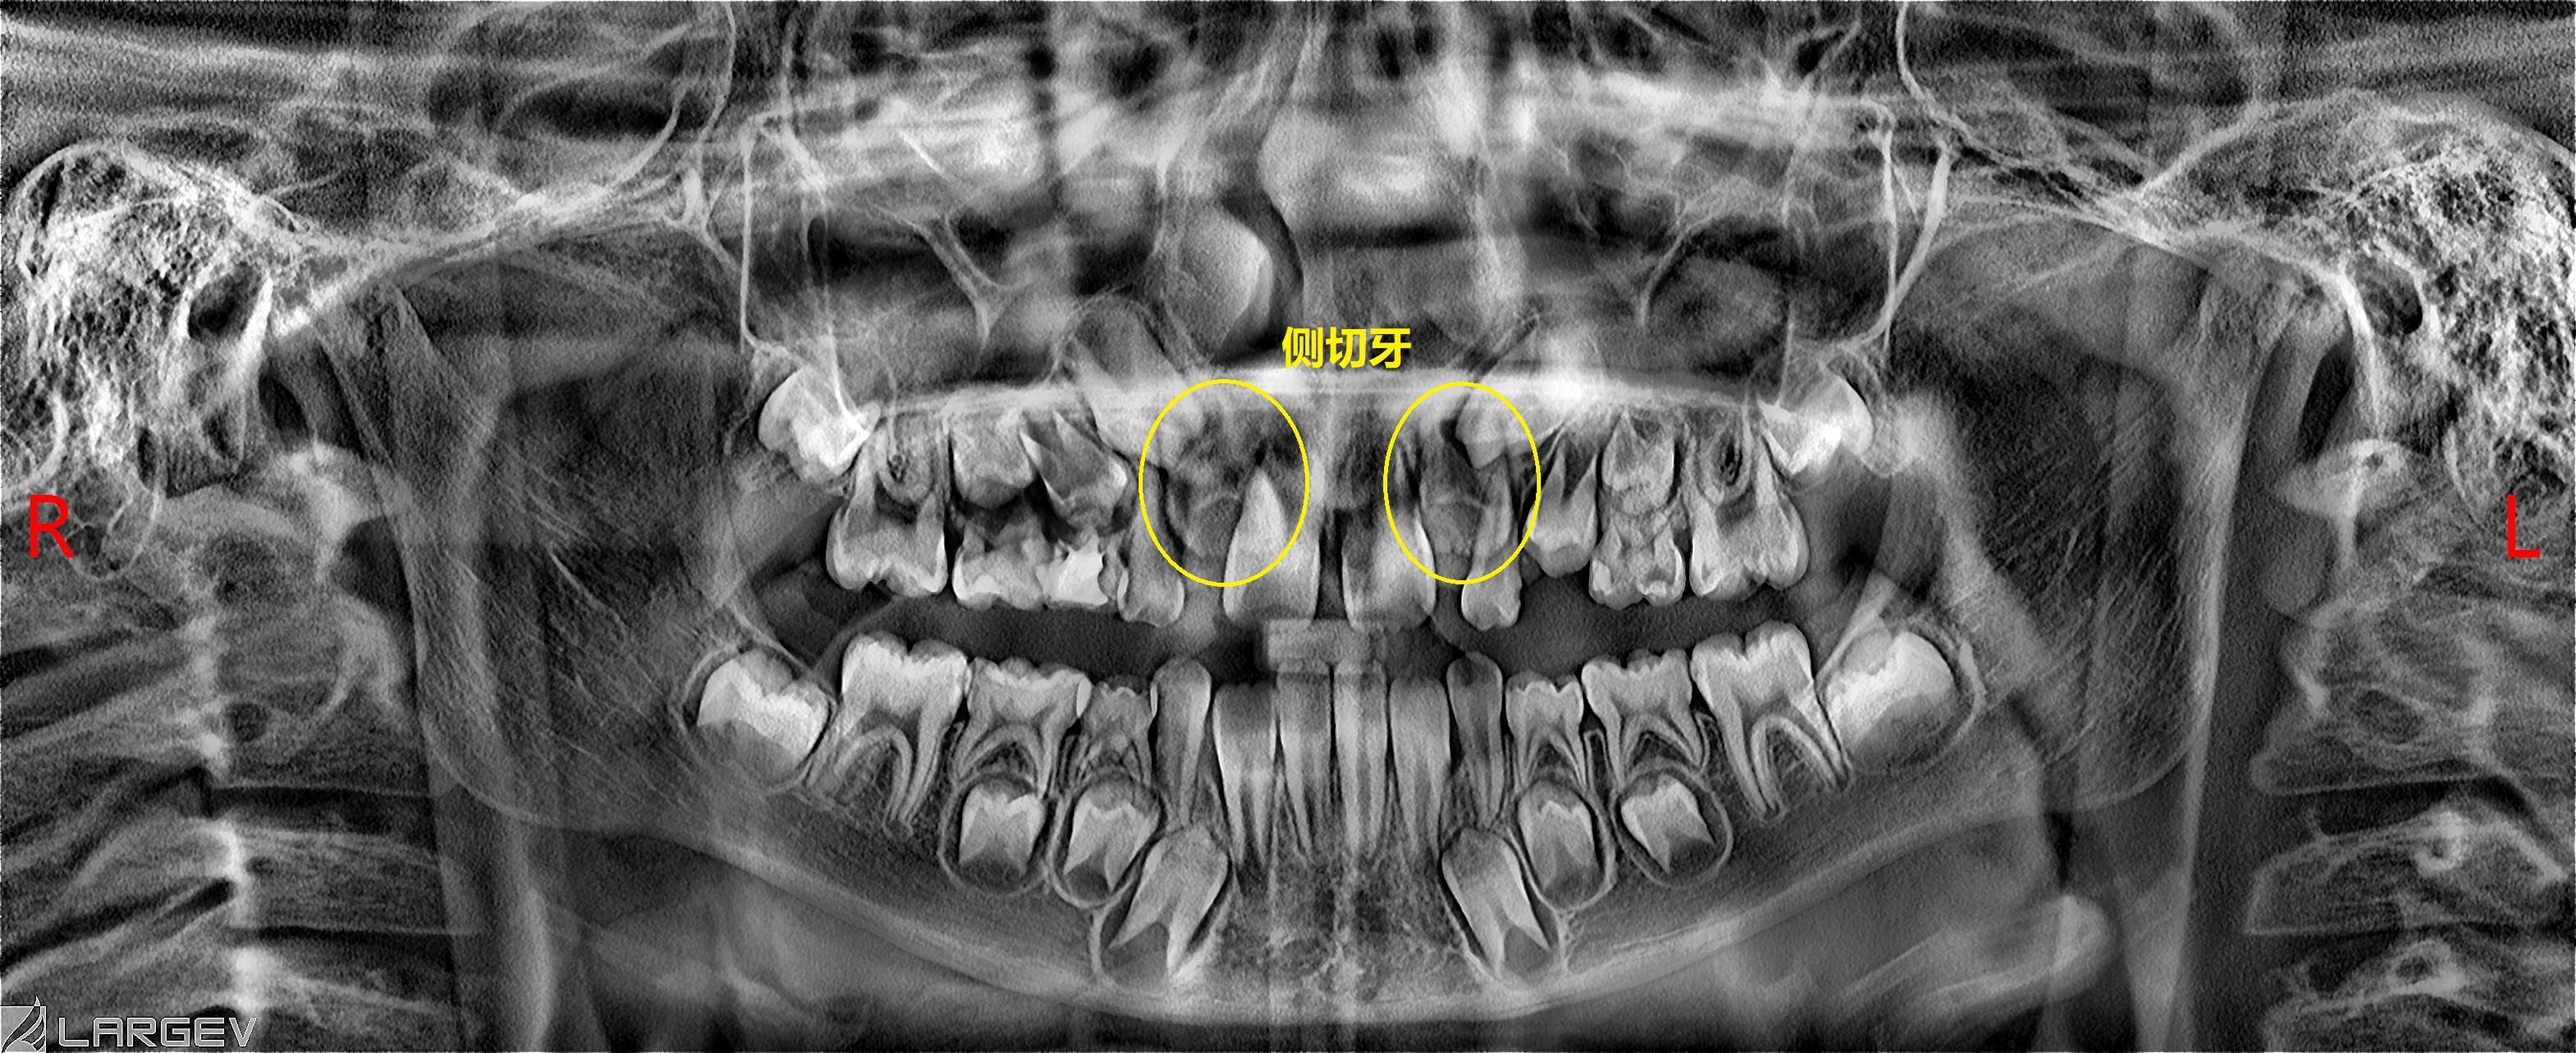

原因一:侧切牙牙胚的挤压

中切牙刚刚萌出,侧切牙的牙胚在牙槽骨内,挤压在中切牙牙根旁,这样就造成中切牙萌出的牙冠向远中倾斜,并且两颗牙中间有个缝。这种情况家长们不用着急,它们会随着侧切牙的萌出有所改善。